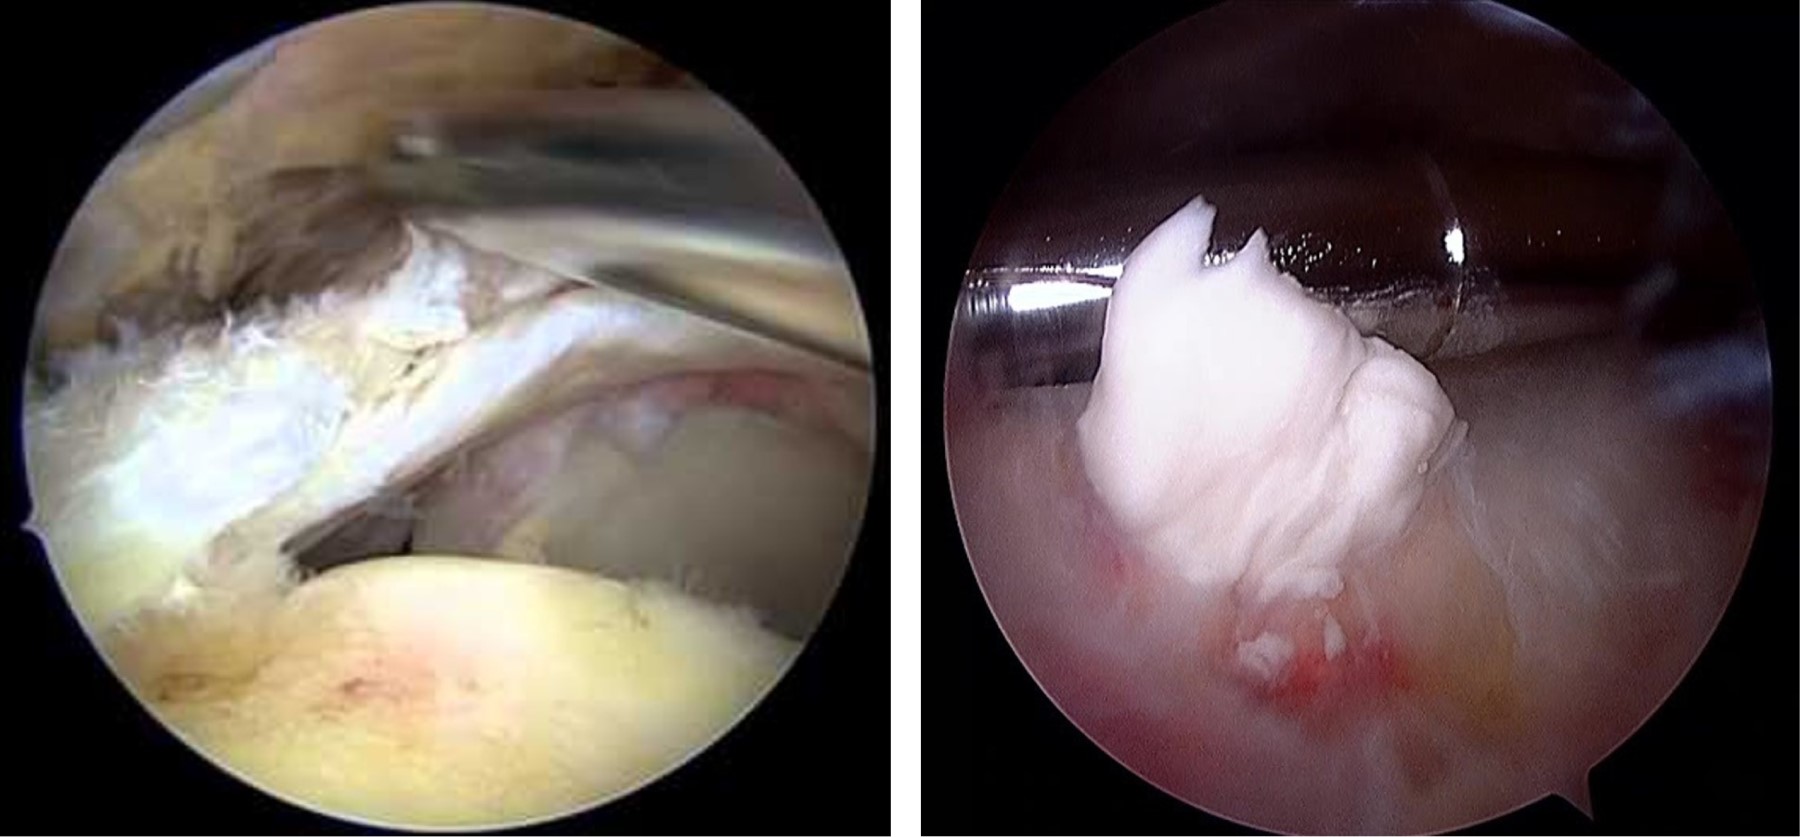

En relación a desaparición de la sintomatología, en este trabajo 17 casos fueron sometidos a punciones y aspiración orientada por ecografía, de los cuales en dos casos (11.7%) se requirió someterlos a artroscopia pues no presentaron mejoría. Al comparar estos resultados con el reporte de Castillo y colegas12 se revelaron mejores, ya que en sus casos reportados 18% requirió de intervención artroscópica (Figura 4).

Figura 3

Figura 4